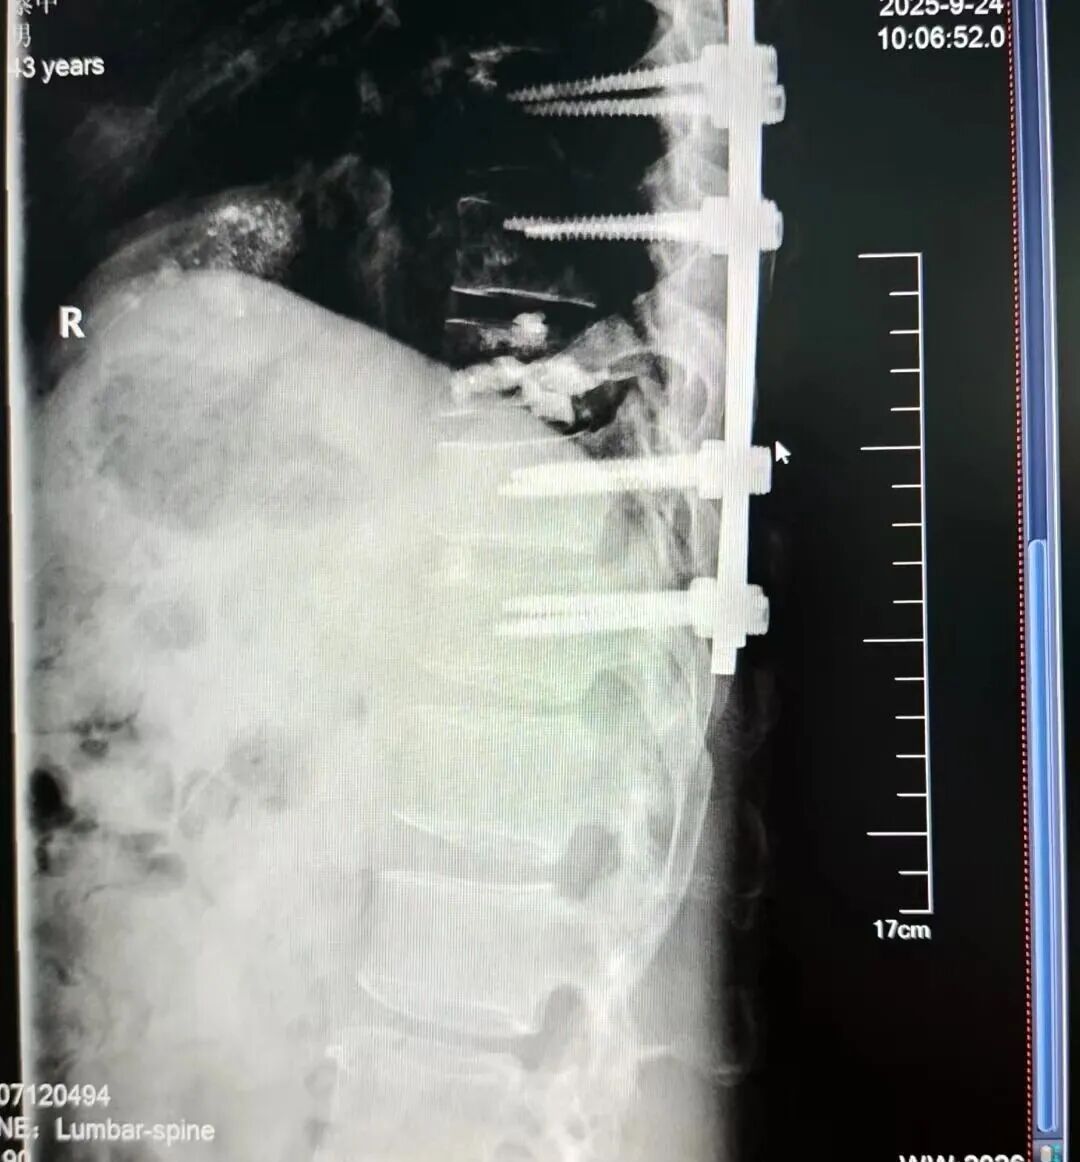

经过细致的病情分析,李清主任团队决定施行一项关键手术:椎体成形术联合钉棒系统内固定术。

手术中,团队会先通过一个微创通道,向已被肿瘤「啃噬」的椎体内,精准注入一种名为「骨水泥」的高分子生物材料。

「这种『骨水泥』进入椎体后,会快速填充被肿瘤破坏的空隙,并在 10 分钟左右凝固。」李清主任形象地介绍,「它的作用,就像用高强度水泥去加固一栋被白蚁蛀空的房梁,能立刻恢复椎体的强度和稳定性,有效灭活肿瘤并缓解疼痛。」

在完成「水泥」补梁后,再通过一套精密的「钉棒系统」,从内部进行固定脊柱,为脊柱重新建立起稳固的支撑。